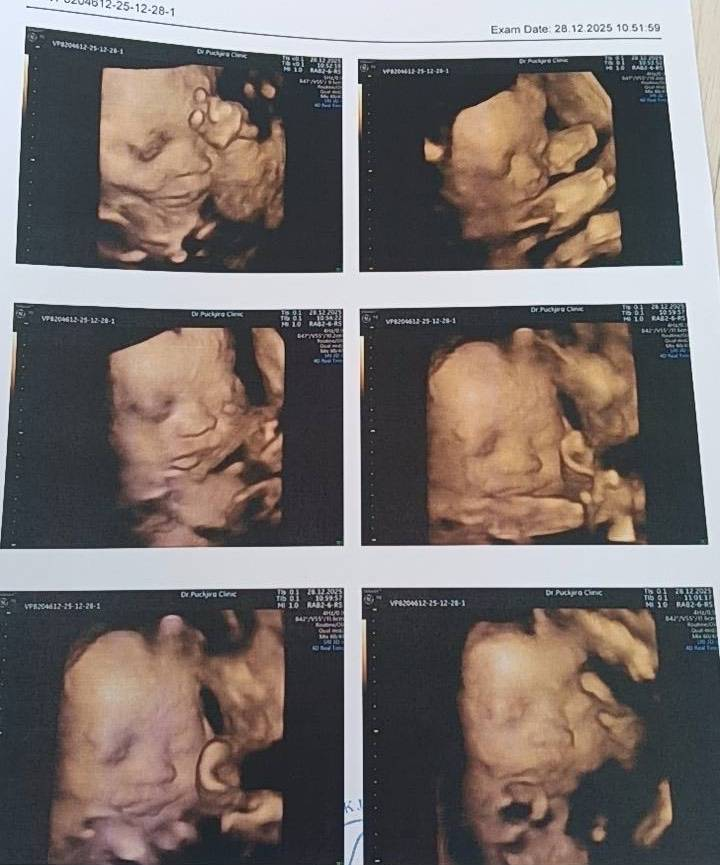

25週、すべて順調、また一人の赤ちゃんが四次元検査を無事に通過しました。すべての発育指標は健康です。これは単なる順調な産検ではなく、まるで小さな天使が世界に向けて発した最初の「健康宣言」のようです。この喜びが続き、間もなくの再会を楽しみにしています。

2月14日、妊娠24週、4Dエコー詳細検査(胎児超音波スクリーニング)で異常なしでした!